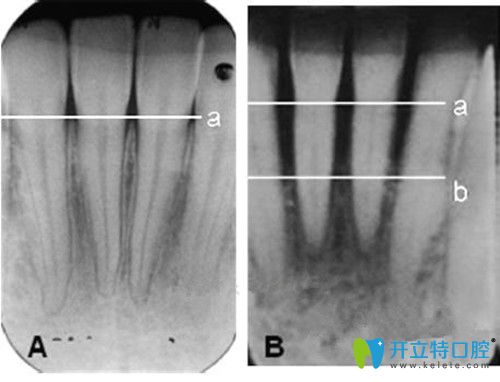

目前種植牙已經(jīng)成為修復(fù)缺牙的主要方法,技術(shù)相對(duì)來說是比較成熟~但是,有些人的種植體周圍牙槽骨組織會(huì)出現(xiàn)吸收、萎縮等情況,下面來詳細(xì)介紹下種植體周圍炎的主要原因有哪些。